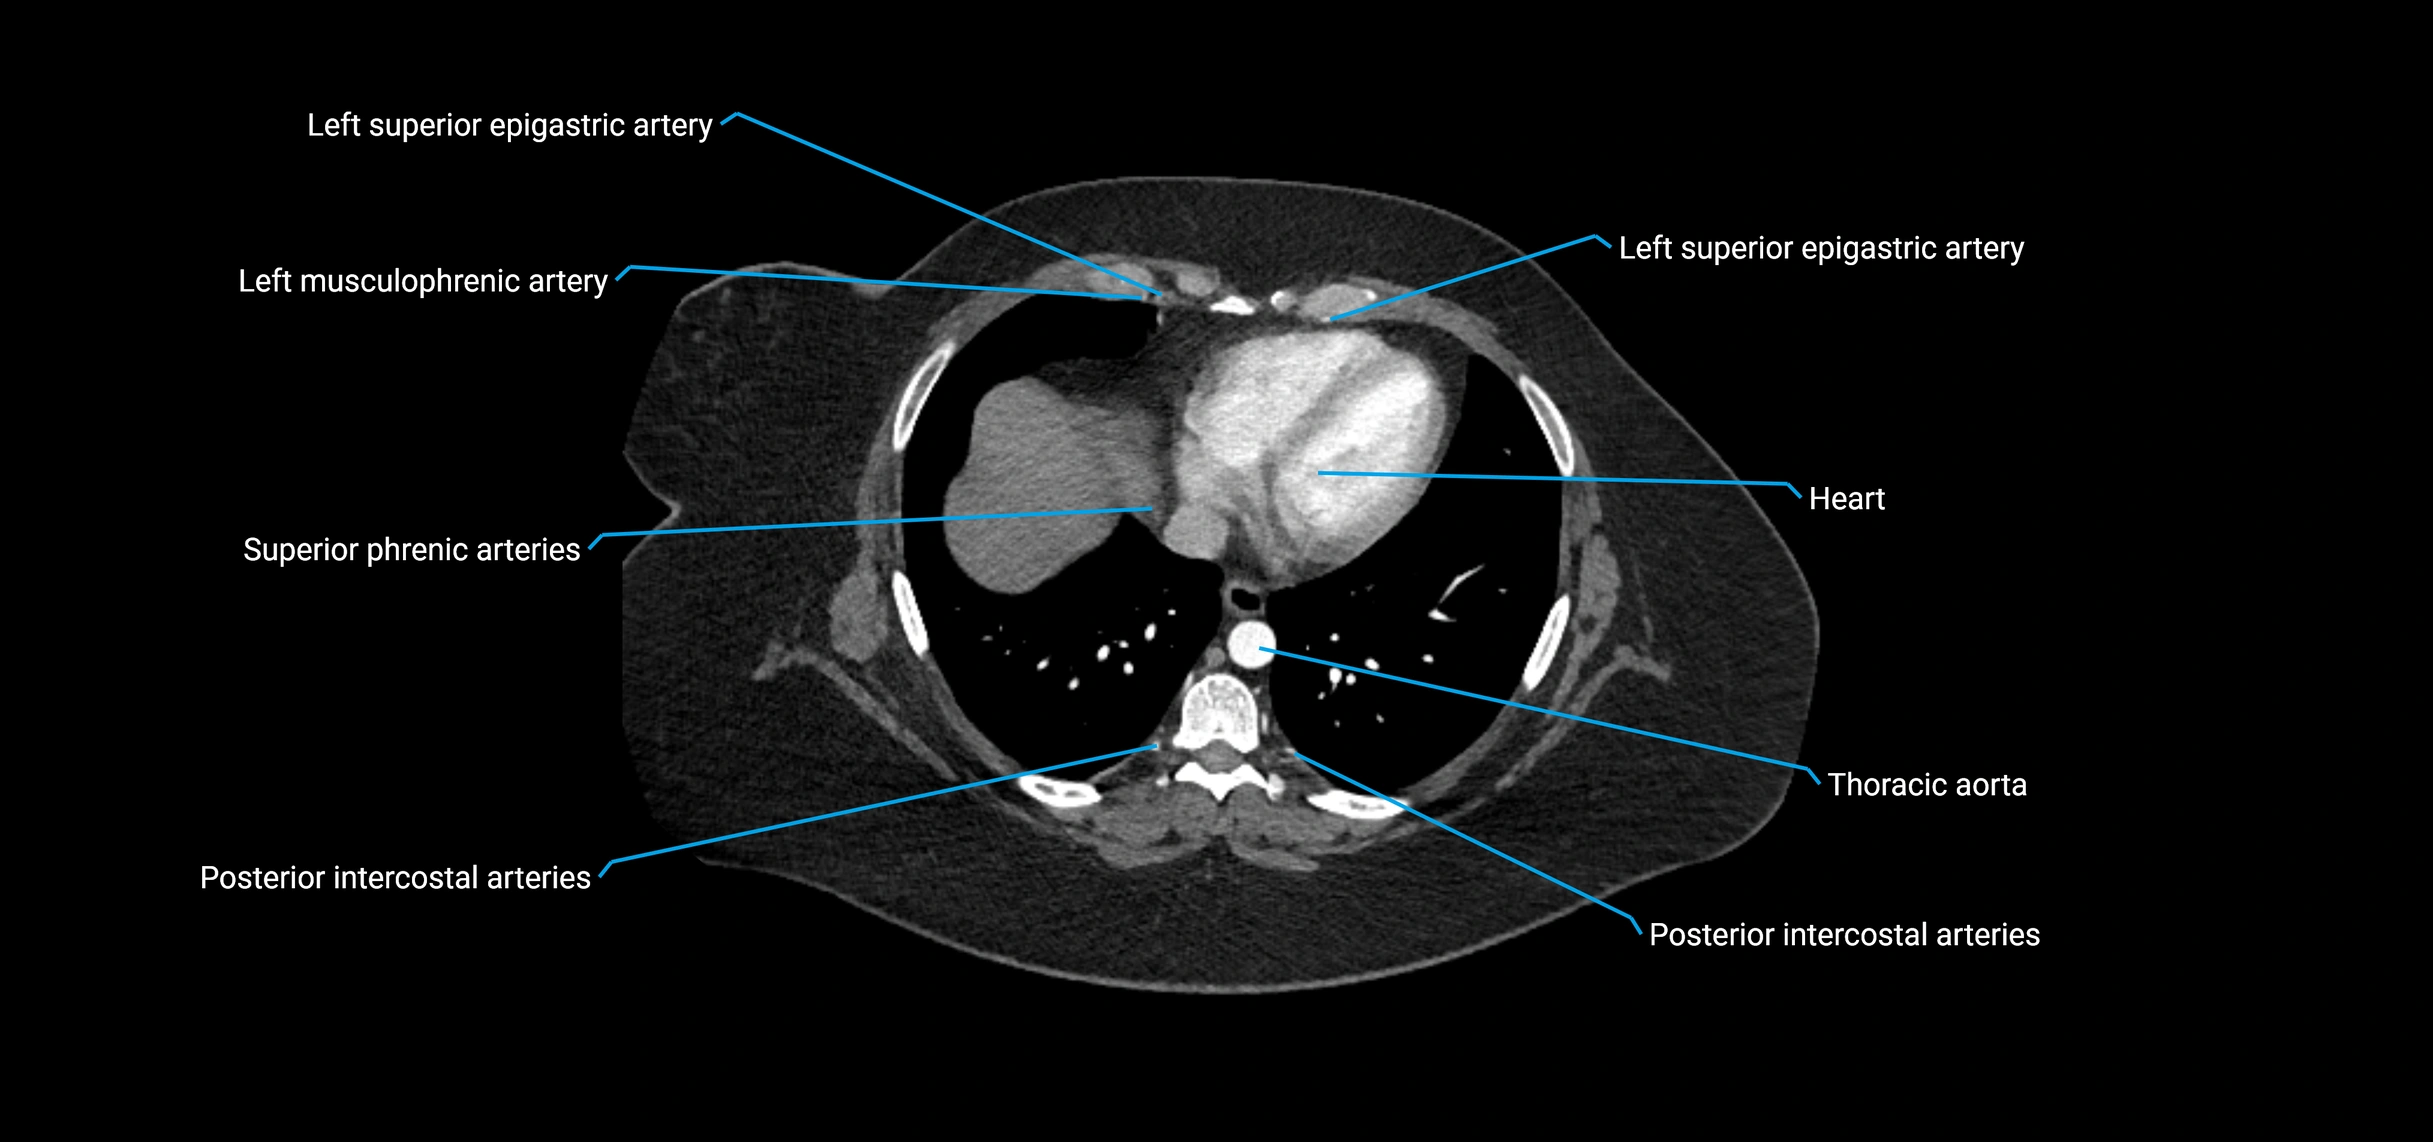

MRI Appearance

T1-weighted images:

• Flowing blood appears as a signal void (black lumen)

• Vessel wall appears as a thin hypointense rim; retroperitoneal fat enhances contrast

T2-weighted images:

• Lumen remains a signal void due to flow

• Adjacent edema, hematoma, or aneurysm wall thrombus may appear hyperintense